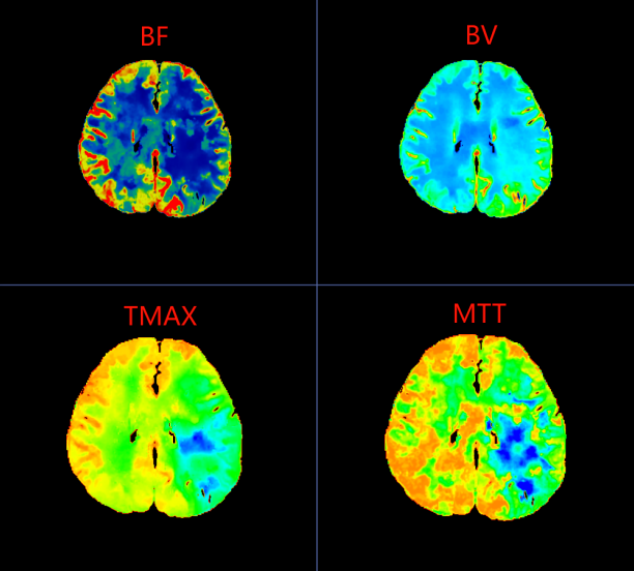

在一脉阳光辽宁影像中心,44岁的李女士(化名)带着持续了40余天的头晕与头痛,完成了一次看似平常却至关重要的检查——脑灌注CTP扫描。图像清晰显示:她左侧大脑中动脉供血区存在明显的低灌注区域,平均通过时间显著延长,脑血流量下降。

诊断结果明确:脑梗死前期I2期改变。这意味着,她的脑血流自我调节机制已开始失代偿,脑组织正处于缺血危机边缘,但梗死尚未真正发生——这是身体发出的最后预警。

在脑梗死真正形成之前,大脑其实已经历一系列血流代偿与失代偿的过程。CTP(CT脑灌注成像)正是一种能够可视化脑血流动力学状态的前沿影像技术。它不仅能显示血管结构,更能精准评估脑组织的血流速度、血流量与血流通过时间,从而在患者尚未出现典型脑梗死症状时,就捕捉到脑灌注异常的“蛛丝马迹”。

李女士的CTP图像中,左侧大脑中动脉供血区呈现的“低灌注”表现,正是脑血流代偿机制开始崩溃的标志。这种梗死前的影像预警,为临床实施超早期干预——如强化抗血小板治疗、控制血压、改善脑灌注等——提供了至关重要的依据,从而有可能阻断病情进展,避免梗死发生。